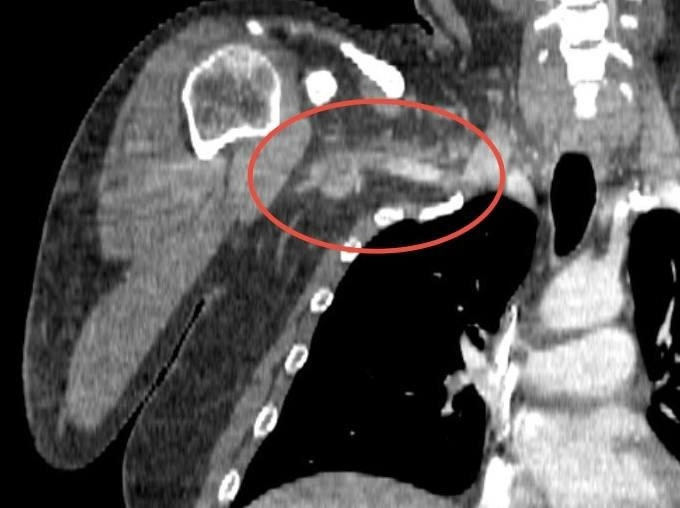

Телеканал 360° сообщает, что у пациента симптомы появились несколько часов назад и со временем нарастали, и он решил обратиться за помощью, когда состояние значительно ухудшилось. Врачи обнаружили отсутствие кровотока в подмышечной, подключичной и плечевой артериях с правой стороны.

Сосудистый хирург Михаил Пырля объяснил, что причиной онемения оказался сгусток тромболитической массы в области плеча. Такое состояние может быть связано с генетическими особенностями, неправильным питанием или нарушением метаболизма. Часто такая патология наблюдаются у пожилых людей.

В ходе полуторачасовой операции врачами был успешно удален тромб с помощью специального баллона, который, расправившись, контролируемо продвинул сгусток в сосуде к разрезу в районе локтевого сгиба. После этого его удалось извлечь с помощью специального крючка. Без операции мужчине грозила ампутация конечности, а в случае отрыва части тромба — угроза для жизни.